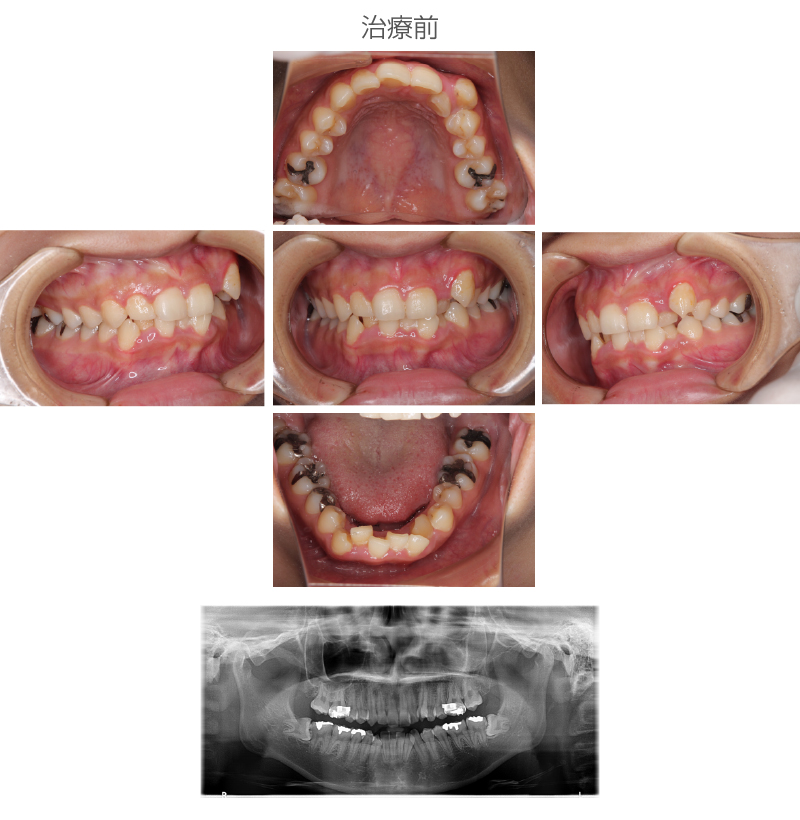

20歳 女性

| 施術名 | マルチブラケット装置による全顎的矯正 |

| 施術の説明 | ワイヤーを使用。 |

施術の副作用 (リスク) |

歯の並ぶスペースが足らないことから上下左右4番目の歯を抜歯する必要があった。 |

| 施術の価格 | 75万円~+消費税 |